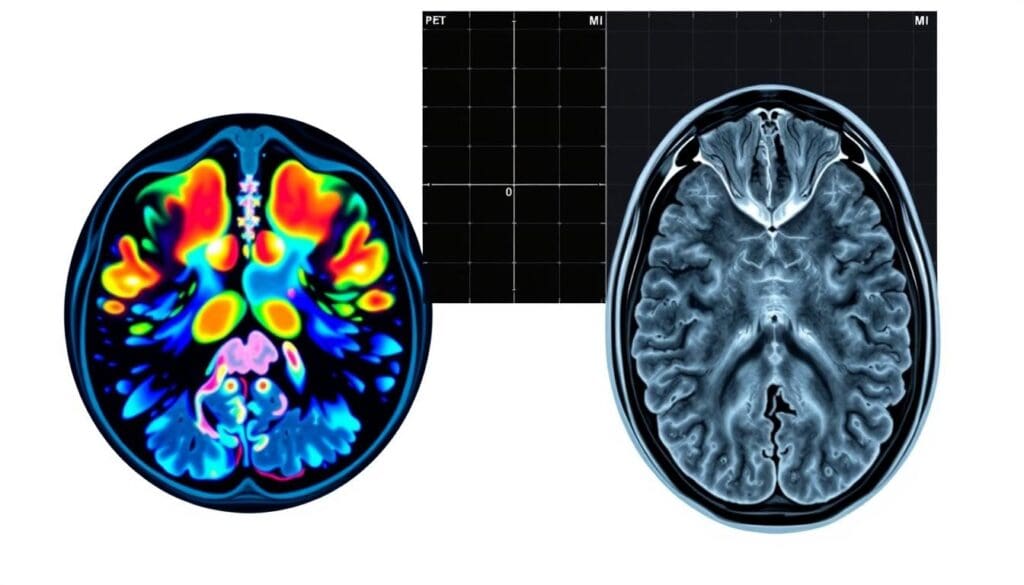

A PET scan detects cancer by measuring how much glucose the cells use, showing areas of high activity where cancer may be present. In contrast, an MRI scan creates detailed images of soft tissues, helping doctors see the exact size, shape, and location of tumors.

When used together — in hybrid PET/MRI machines — these scans give a more complete view of the body, improving the accuracy of cancer detection and treatment decisions.